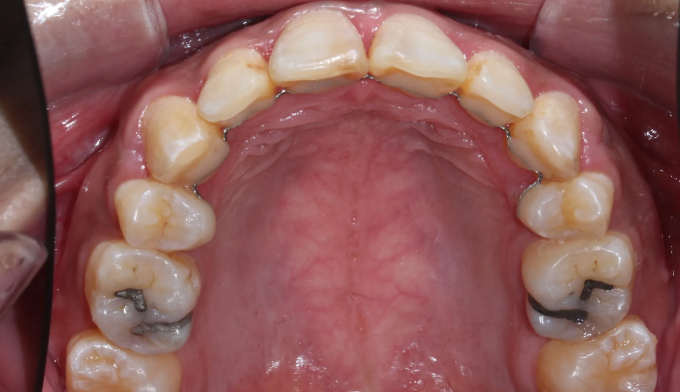

뻐드러진 앞니로 인한 돌출입과, 구강위생관리 부족으로 인한 다수의 충치가 관찰된 케이스입니다.

교정치료는 24개월 소요되었으며, 뻐드러진 앞니로 인해 다물기 어려웠던 입술도 이제는 편하게 다물 수 있게 되었습니다.